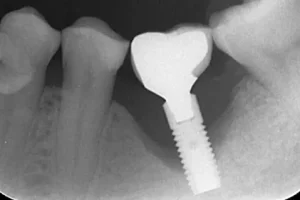

Fotos de implantes dentales mal colocados: por qué es importante el diagnóstico

Las fotos de implantes dentales mal colocados (radiografías o escáner 3D) permiten detectar problemas de posición, pérdida ósea o infección que pueden provocar el fracaso del implante.

Un diagnóstico preciso es clave para decidir la mejor solución.